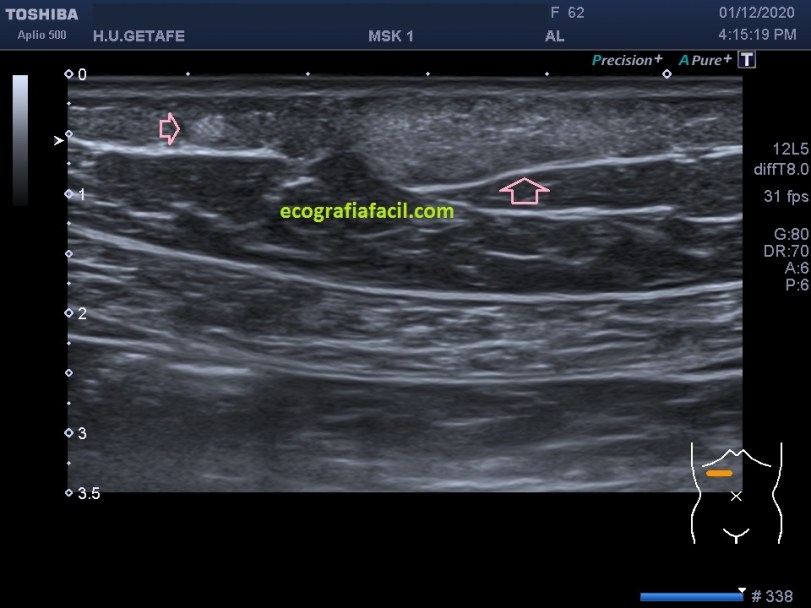

La estructura que estamos estudiando en este Caso 1, en las imágenes 1 a 6, es el estudio de protocolo de cualquier lesión, localización (flechas rosas), medición, vascularización. La 7 te marca una situación habitual en el estudio de los lipomas, y es que la paciente se nota un bulto, pero en la misma exploración descubrimos más, como es la pequeña lesión hiperecogénica que está justo al lado de la lesión mayor y palpable. Algunos de ellos, repito, pueden ser imperceptibles para la paciente, como era este caso. La imagen 8 es otra lesión próxima que sí era palpable.

En este caso las lesiones son todas hiperecogénicas comparativamente con el tejido hipoecogénico de la grasa del tejido celular subcutáneo. Son más o menos ovaladas, su eje largo es paralelo a la piel, no tienen vascularización y tienen medidas distintas. El diagnóstico final fue de lipomas. La paciente tenía más en la extremidades.

Cuidado, estas lesiones pueden presentarse hipoecogénicas, en ocasiones es complicado encontrarlos y es el reborde el que nos marca la posición de la lesión.